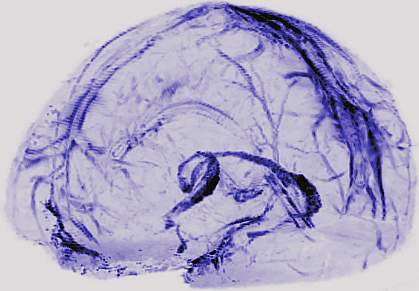

How the brain clears waste and fights infections, however, has been a mystery. Although the human brain has blood vessels, there was no evidence it has a lymphatic system. Recently, studies in mice found evidence of the brain’s lymphatic system in the dura, the brain's leathery outer coating.

The researchers first injected gadobutrol, a magnetic dye with molecules small enough to leak out of blood vessels in the dura into lymphatic vessels, but too big to pass through the blood-brain barrier and enter other parts of the brain. With this dye, MRI images showed brightly lit blood vessels throughout the dura. The researchers then looked for vessels surrounding the blood vessels using different MRI techniques. They were able to see smaller but almost equally bright spots and lines that tracked along the blood vessels. They found these lymphatic vessels in all five human volunteers and all three monkeys.

The researchers also looked at the suspected lymphatic vessels in autopsied human and monkey brain tissue. They found that the vessels contained specific cells and protein markers that are unique to lymphatic vessels and distinguished them from blood vessels. These findings suggest the lymphatic system is a common feature of mammalian brains.